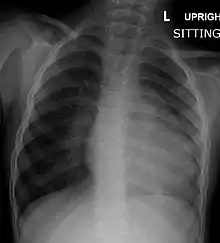

Chest radiograph

Before more sophisticated techniques became available, chest X-ray was the definitive method of diagnosis. The abnormal "coeur-en-sabot" (boot-like) appearance of a heart with tetralogy of Fallot is classically visible via chest X-ray, although most infants with tetralogy may not show this finding.[49] The boot like shape is due to the right ventricular hypertrophy present in TOF. Lung fields are often dark (absence of interstitial lung markings) due to decreased pulmonary blood flow.[50]: 171–72